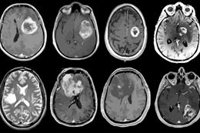

Los cánceres asociados al tabaquismo que se evaluaron en este estudio incluían los de cavidad oral, faringe, esófago, estómago, colorrectal, hígado y conducto biliar intrahepático, páncreas, laringe, pulmón y bronquios, cuello uterino, riñón y pelvis renal, vejiga urinaria y leucemia mieloide aguda.